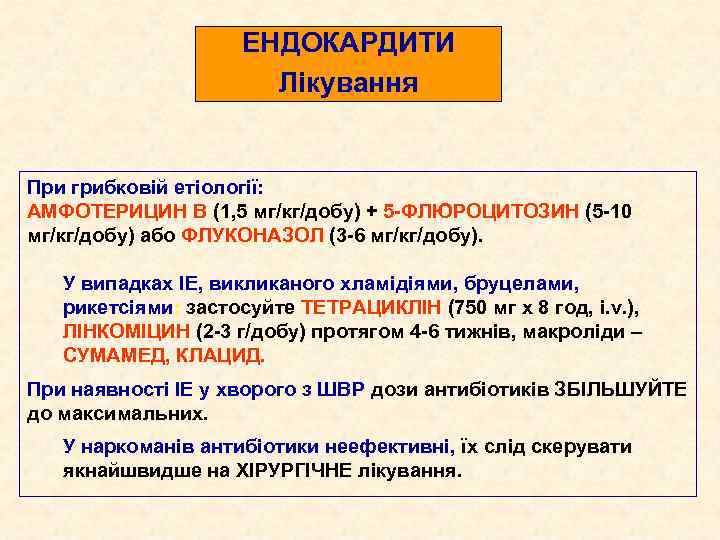

ЕНДОКАРДИТИ Лікування При грибковій етіології: АМФОТЕРИЦИН В (1, 5 мг/кг/добу) + 5 -ФЛЮРОЦИТОЗИН (5 -10 мг/кг/добу) або ФЛУКОНАЗОЛ (3 -6 мг/кг/добу). У випадках ІЕ, викликаного хламідіями, бруцелами, рикетсіями: застосуйте ТЕТРАЦИКЛІН (750 мг х 8 год, і. v. ), ЛІНКОМІЦИН (2 -3 г/добу) протягом 4 -6 тижнів, макроліди – СУМАМЕД, КЛАЦИД. При наявності ІЕ у хворого з ШВР дози антибіотиків ЗБІЛЬШУЙТЕ до максимальних. У наркоманів антибіотики неефективні, їх слід скерувати якнайшвидше на ХІРУРГІЧНЕ лікування.